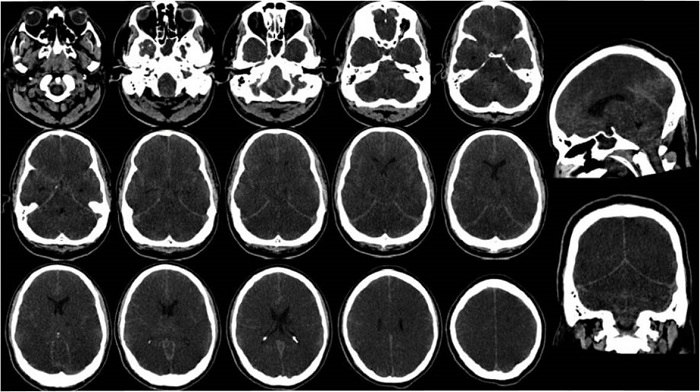

Neuroimágenes y diagnósticos diferenciales en otras manifestaciones neurológicas

Con la presentación de manifestaciones neurológicas, las neuroimágenes son de utilidad en la evaluación de diagnósticos diferenciales. En el caso de pacientes con COVID-19 severo se han descrito tres patrones predominantes: alteraciones de la señal localizadas en el lóbulo temporal medial, lesiones hiperintensas de la sustancia blanca multifocal no confluente en Flair y difusión con realce variable, asociadas a lesiones hemorrágicas y microhemorragias de sustancia blanca extensas y aisladas, estas últimas asociadas con un peor estado respiratorio, neurológico y biológico estado respiratorio, neurológico y biológico 66.

En un estudio multicéntrico en el que se incluyeron 64 pacientes con manifestaciones neurológicas y un estudio de RMN se describieron hallazgos que se clasificaron en tres grupos: 1) ACV isquémico: a) infartos de arterias grandes, b) infartos limítrofes, c) infartos lacunares, y d) hipóxico isquémico; 2) encefalitis: a) encefalitis límbica, b) lesión citotóxica del cuerpo calloso (CLOCC), c) encefalomielitis aguda diseminada radiológica (ADEM), d) encefalopatía necrotizante hemorrágica aguda, y e) encefalitis miscelánea; 3) realce leptomeníngeo. De este grupo de pacientes, 36 (el 56 %) resonancias magnéticas cerebrales se consideraron anormales, posiblemente relacionadas con el SARS-CoV-2. Los accidentes cerebrovasculares isquémicos (27 %) y la encefalitis (13 %) fueron los hallazgos de neuroimagen más frecuentes. Se observó realce leptomeníngeo en las secuencias Flair y ponderadas en T1 poscontraste. Entre las ocho encefalitis, se describieron dos casos de encefalitis límbica, dos casos de encefalopatía necrosante hemorrágica aguda radiológica, dos casos de encefalitis miscelánea, un caso de ADEM radiológica y un caso de CLOCC 67.

Respecto a este último grupo de manifestaciones, el SARS-CoV-2 debería incluirse en el diagnóstico diferencial de encefalitis junto con otros virus neurotropos. Los síntomas usuales incluyen fiebre, cefalea, crisis epilépticas, trastornos conductuales y alteración del estado de conciencia 68. El primer paciente descrito, de veinticuatro años, debutó con cefalea y odinofagia, posterior alteración del estado de conciencia y crisis convulsivas; se realizó la detección del virus en muestra de LCR, con hallazgos imagenológicos dados por hiperintensidad del lóbulo temporal mesial derecho e hipocampo 69. Asimismo, se describió un caso de encefalopatía necrotizante aguda hemorrágica como complicación asociada en una paciente de 58 años que consulta por un cuadro de tres días de tos, fiebre y alteración del estado de conciencia, con PCR positivo para COVID-19 y negativo para el virus del herpes simple 1 y 2, el virus del Nilo occidental y el virus de la varicela zóster. La RMN cerebral demostró lesiones que realzan en tálamos bilaterales, con componente hemorrágico en secuencia de susceptibilidad e hiperintensidad en los lóbulos temporales mediales y las regiones subinsulares.

Los hallazgos en LCR de una cohorte de seis pacientes con observaciones en neuroimagen sugestivos de encefalopatía mostraron marcadores de inflamación: cuatro tenían pleocitosis, cinco niveles altos de proteína, dos tenían inmunoglobulina G elevada y otro tenía bandas oligoclonales idénticas en LCR y suero, destacando en ellos que el análisis RT-PCR SARS-CoV-2 fue negativo 67, por lo que en el contexto descrito la sospecha clínica debe orientar a evaluar este diagnóstico.

Otros hallazgos a destacar en este grupo es la presencia de lesiones citotóxicas del cuerpo calloso (CLOCC), entendido como un trastorno clínico-radiológico, caracterizado por una encefalopatía leve transitoria y una lesión reversible del cuerpo calloso, predominante en el esplenio, relacionadas con edema citotóxico, por los mecanismos mediados por citocinas previamente descritos 67.